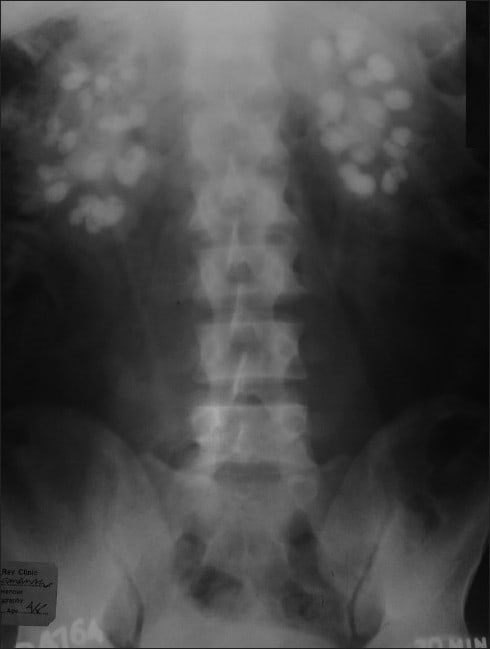

"Right-sided crossed kidney ectopy without fusion in a 13-year-old girl (confirmed with CT images). "

Importantly, DMSA scans are taken with a Gamma camera behind the patient, therefore the left kidney typically appears on the left side of the image and the right kidney appears on the right side of the image. With that in mind, this DMSA shows a left kidney in the normal position with a right kidney that has crossed the midline and appears in continuity with the left. As the right kidney has crossed the midline this would be called a right sided fused ectopic kidney.

Crossed fused kidney is the second most common congenital fusion abnormality with an incidence between 1/1300-1/7500, after Horseshoe kidney which is much more common with an incidence of around 1/400. Crossed fusion kidneys typically occur where the ectopic kidney that has crossed the midline is fused to a kidney in its normal position. Crossed fused kidneys are typically asymptomatic.

Of crossed fused kidney's McDonald and McClellan classified six types, shown in the answer image below. The most common of these is unilateral fused kidney with inferior ectopia, with unilateral fused kidney with superior ectopy being the least common.